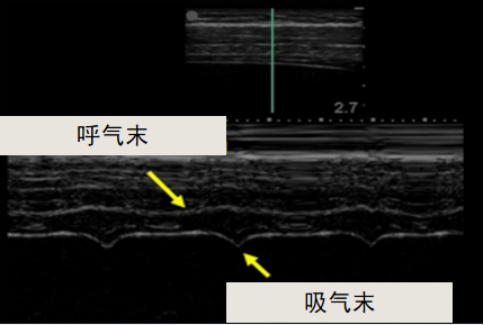

临床中最简单的评估膈肌功能的方法是肺活量。当我们在临床上考虑患者可能存在膈肌功能损伤时,通常会关注其肺活量(VC)/用力肺活量(FVC)。正常情况下,立位VC/FVC约为50 ml/kg,但卧位时的VC/FVC低于立位。如果卧位VC/FVC较立位下降超过20%,考虑存在膈肌功能下降;如果卧位VC/FVC较立位下降超过30%,考虑存在膈肌麻痹。上述情况仅为“考虑”而非明确诊断,是因为肺活量的主观性比较强。膈肌分为左右两叶,肺功能监测不能发现单侧膈肌麻痹或者单侧膈肌功能下降。因为如果存在单侧膈肌麻痹,健侧膈肌功能通常会代偿,可能会导致患者肺功能是正常的。所以临床中我们会选择最大吸气压(MIP)进行监测,并且多在RV体位时进行,随着年龄的增长,MIP呈下降趋势。MIP<60 cmH2O,考虑存在膈肌功能下降;MIP<30 cmH2O,考虑存在膈肌麻痹。膈肌超声目前在膈肌功能评估方面得到广泛应用,它是通过测量膈肌厚度(形态)和膈肌移动度(运动)来评估膈肌功能。膈肌厚度一般通过测量吸气末膈肌厚度、呼气末膈肌厚度、膈肌厚度变异率(Tdi)获得;膈肌移动度一般通过测量平静呼吸、深吸气、吸鼻动作(Sniff动作)获得。膈肌两侧是与胸壁贴合的肌纤维,随着膈肌随着呼气和吸气而上下移动,会导致膈肌厚度的差异(图5),进而衍生出Tdi,计算公式为:Tdi=(膈肌厚度吸气末-膈肌厚度呼气末)/膈肌厚度呼气末。并且Tdi与肺容量的匹配性非常好。现有各项研究对Tdi的正常值报道不一,目前使用较多的数值是:平均呼气末膈肌厚度:女性为1.4±0.3 mm,男性为1.9±0.4 mm。所以,若呼气末膈肌厚度>2 mm,Tdi>35%,判断为正常;若Tdi<20%,则判断为膈肌麻痹。这些数据多是基于欧美人群的研究,由于体质差异等,我国人群膈肌厚度通常<2 mm。所以我们认为在评估膈肌功能方面,Tdi比膈肌厚度更准确。通常我们将探头置于锁骨中线与肋下缘的交界处来观测膈肌的上下位移。吸气时,膈肌下移,会贴近探头,形成向上的波形;呼气时,膈肌远离探头,形成向下的波形;由此反映出膈肌的移动。通过超声可以看到正常人在平静呼吸、Sniff动作以及深呼吸时的膈肌移动范围。如果膈肌麻痹,超声会观察到膈肌明显下移,或者当患者吸气时,膈肌不下移,反而上移,形成负向波形,出现矛盾运动,此时也考虑患者存在膈肌麻痹(图6)。膈肌移动度正常参考值:①平静呼吸时膈肌移动度:男性为1.8±0.3 cm;女性为1.6±0.3 cm;②最大深吸气时膈肌移动度:男性>4.7 cm,女性>3.7 cm;③Sniff动作时膈肌移动度:男性>1.8 cm,女性>1.6 cm;④膈肌移动度于平静呼吸时<1 cm,提示存在膈肌功能减弱/膈肌麻痹。跨膈压(Pdi)计算公式为:Pdi=胸膜压(Ppl)-腹内压(Pab)。临床中可以用食道囊管和多功能胃管分别留置于食道中下1/3与胃内来监测食道压(Pes,等同于Ppl)和胃内压(Pag,等同于Pab)(图7)。Pdi正常值为3~12 cmH2O。由于存在穿刺过程中发生气胸的风险,因此膈肌肌电图在临床应用并不普遍。